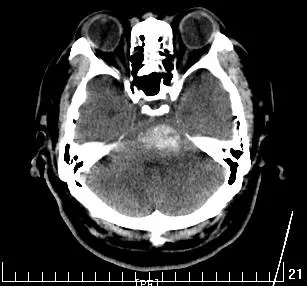

56岁张先生以“突发意识不清伴呕吐30分钟”入院,头颅CT提示:脑干出血6ml。查体:中昏迷,刺痛过伸,鼾式呼吸,双侧瞳孔不等大,左侧直径3mm,右侧直径约2mm,对光反应消失,四肢肌张力高,病理征阳性。

入科后,谢国强主任团队立即予以患者气管插管,持续呼吸机辅助呼吸,镇痛镇静治疗,仔细阅片后,急诊在局麻下行脑干出血穿刺置管引流术,术后引流管位置良好,予以尿激酶溶解血凝块,加快血肿引流。血肿清除效果良好。术后7天拔除头部引流管,12天撤除呼吸机,目前患者生命体征平稳,自动睁眼,正在进一步康复中。